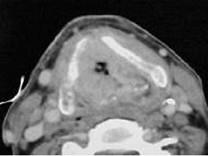

男,55岁,声嘶6年,有长期吸烟史。检查:无呼吸困难。喉镜检查:声带慢性充血,可见右侧声带可见菜花样新生物,右侧声带活动固定,喉部CT检查如下图:诊断...

问题 男,55岁,声嘶6年,有长期吸烟史。检查:无呼吸困难。喉镜检查:声带慢性充血,可见右侧声带可见菜花样新生物,右侧声带活动固定,喉部CT检查如下图: 诊断首先考虑 ( )